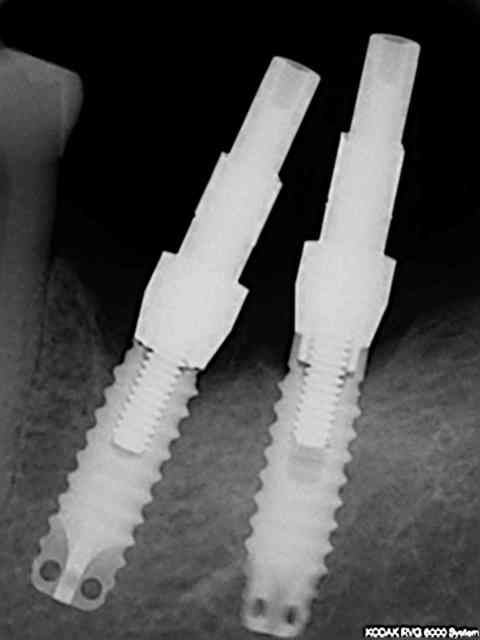

en regardant la rvg avec le col cassé on s'aperçoit que le filetage va bien plus loin que la vis donc j'ai présumé que je pourrai visser plus loin dans le fût.

modification du transfert:

en supprimant l'octogone du transfert totalement la vis va bien à fond (rvg jointe) mais par contre le transfert n'est pas en butée contre l'implant modifié donc j'ai modifié légèrement la vis pour qu'elle pousse le tansfert contre l'implant (ajout d'un petit anneau de duralay sur les premières spires ) de sorte qu'en vissant on soit bien en butée contre le fût (cf deuxième rvg)

puis j'ai controlé lors de l'essayage de l'armature que l'ensemble soit vraiment passif.

A priori ras mais ce cas n'a été possible que grace à la profondeur de filetage du fut .